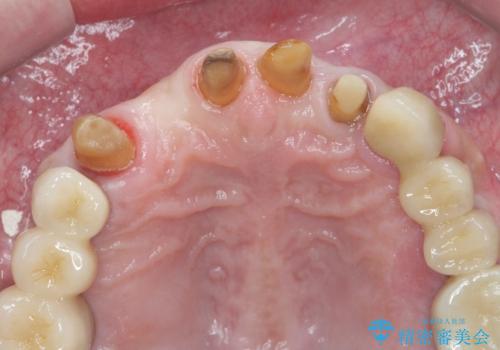

歯周病治療を伴う前歯審美セラミック治療

- 前歯の見た目をなんとかしたい、とセラミック治療を希望され来院されました。

セラミック治療を行う前に歯周病の問題を解決すべく歯周外科を行い歯周ポケットを除去し整備したのちセラミックブリッジ・クラウンの製作を行います。